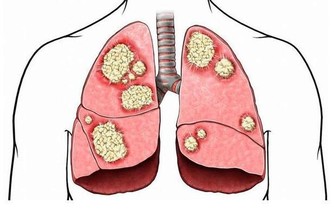

細胞癌變的部位不同,導致的貧血類型也會有所差異。

例如骨髓細胞發生癌變時,會直接影響人體生產紅細胞的能力,造成嚴重貧血;

而多數結腸癌患者是因為消化道出血過多引起了貧血。

結腸腫瘤會釋放出特殊的化學物質,影響新血管的形成;

隨著腫瘤的生長,還會導致腸道內壁的血管破裂,引起內出血。

內出血不僅會導致大量紅細胞流失,還有可能造成缺鐵。

這是因為破裂的血管會誘發炎症,而炎症所產生的免疫細胞會吸附血液中的鐵。

隨著炎症的擴散,患者體內的鐵元素含量會逐漸減少,從而誘發缺鐵性貧血。